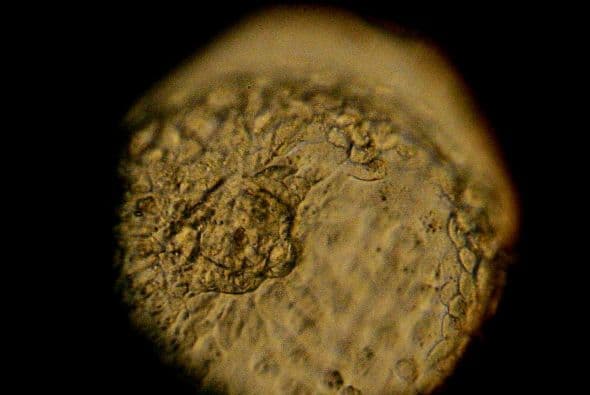

1 - Investigadores japoneses transformaron células madre embrionarias de ratón en ovocitos viables que pudieron ser fecundados en laboratorio y se desarrollaron para dar ratones entre madres portadoras, una técnica que les devuelve la esperanza a las mujeres infértiles.